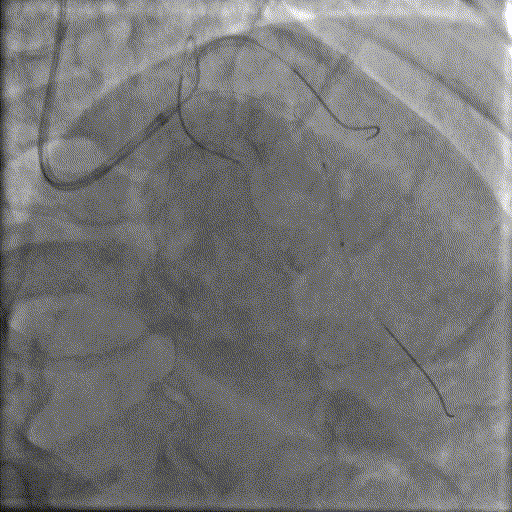

LAD处理:

球囊预扩

用预扩球囊扩张LAD病变,支架无法通过。为了解血管病变分布情况及钙化程度,遂启用IVUS检查。

术前腔内影像学IVUS指导

IVUS提示LAD近中段钙化病变,中段可见360°环形钙化。

冲击波球囊治疗

3.0x12@4atm 冠脉血管内冲击波导管顺利推送至前降支近端,但无法通过成角钙化处,故于血管近端就地进行10个周期治疗,复查造影见近端狭窄明显减轻;再次选择2.5x12@4atm冠脉血管内冲击波导管推送至成角钙化处,逐步掘进扩张病变并给予冲击波治疗,最终顺利通过成角钙化处,并于前降支中段再次进行10个周期的冲击波治疗。

支架植入并后扩

于LAD近中段串联植入两枚药物洗脱支架,经非顺应性球囊后扩张支架,复查造影及IVUS提示支架膨胀完全,贴壁良好,无夹层撕裂。